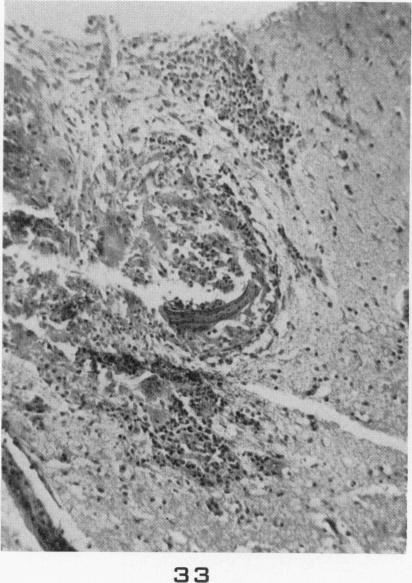

Visceral larva migrans; with a case report.

Am J Pathol. 1956 Jul-Aug;32(4):777-803.